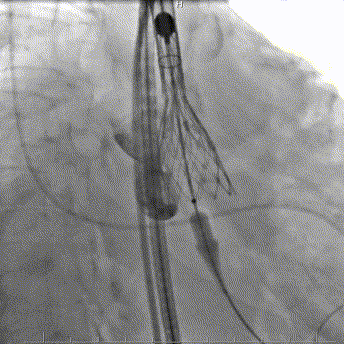

释放定位

最终释放